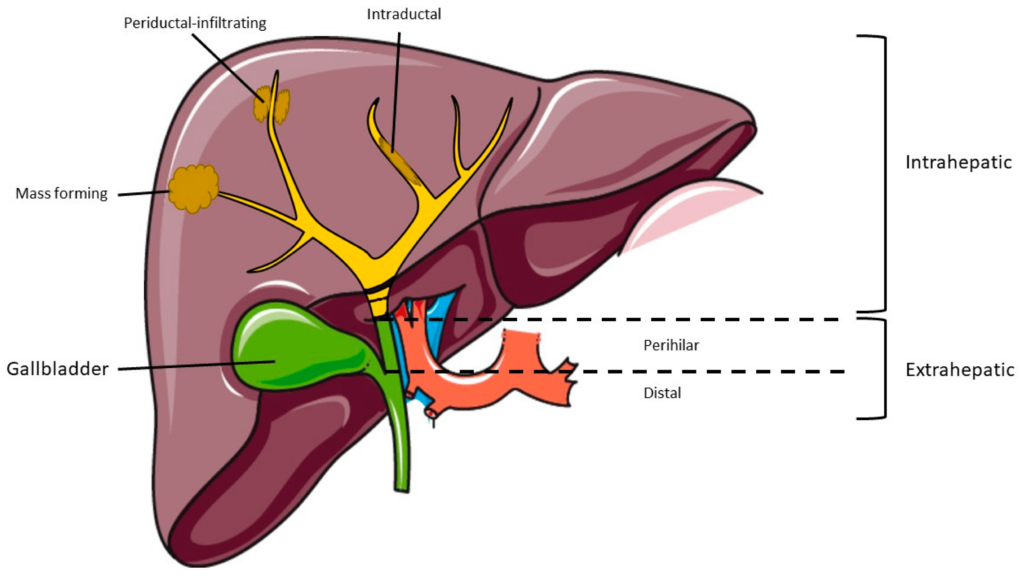

8. Cholangiocarcinoma

Cholangiocarcinoma is a rare cancer that originates in the bile ducts, which are responsible for transporting bile from the liver to the small intestine. It can occur within the liver (intrahepatic) or outside the liver (extrahepatic).

Number of people affected yearly: Cholangiocarcinoma is considered a rare cancer, but its incidence varies in different regions of the world. According to global estimates, there are around 5,000 to 10,000 new cases of cholangiocarcinoma diagnosed each year.

Area of the body affected: Cholangiocarcinoma originates in the bile ducts, which are responsible for carrying bile from the liver to the small intestine. It can occur in different parts of the bile ducts, including within the liver (intrahepatic) or outside the liver (extrahepatic).

Survival rate: The survival rate for cholangiocarcinoma depends on several factors, including the stage of the cancer at diagnosis and the treatment options available.

Unfortunately, cholangiocarcinoma is often diagnosed at an advanced stage when curative treatments are less effective. The overall 5-year survival rate for cholangiocarcinoma is relatively low, ranging from around 5% to 30%, depending on the stage of the cancer and the treatment received.